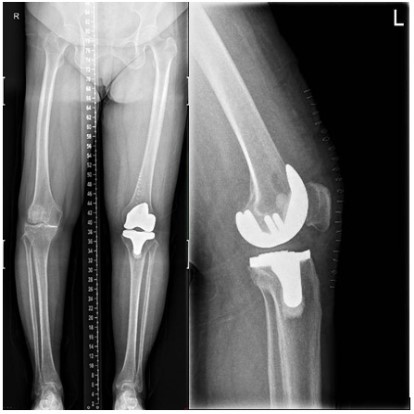

The patient came back again to the hospital 4 months following TKR, and complained of pain in her right hip for a month. Clinical examination and X-ray film: show the diagnosis of fracture of the right femoral neck, The patient denied any traumas (Figure 3).

Figure 3: Case 1 fracture of the right femoral neck

The patient returned again nearly one year later, and complained of pain in her left hip for 20 days, especially during movement. Clinical examination and X-ray film; made the diagnosis of fracture of the left femoral neck. Also, the patient did not suffer any trauma (Figure 7).

Figure 7: Case 2 fracture of the left femoral neck